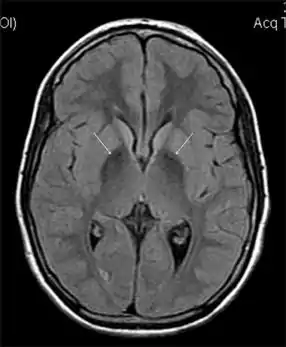

| MRI hypointensity (white arrows) in the globus pallidi that indicates the presence of iron deficiencies which would be seen in a diagnosis of Aceruloplasminemia | |

Diagnosis of this disorder depends on blood tests demonstrating the absence of serum ceruloplasmin, combined with low serum copper concentration, low serum iron concentration, high serum ferritin concentration, or increased hepatic iron concentration. MRI scans can also confirm a diagnosis; abnormal low intensities can indicate iron accumulation in the brain.[5]